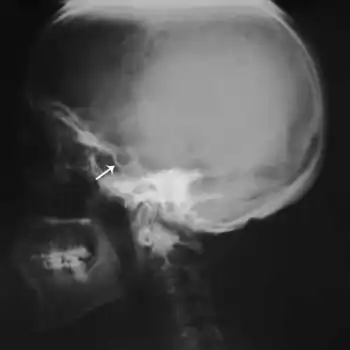

Mulibrey nanism ("MUscle-LIver-BRain-EYe nanism") is a rare autosomal recessive congenital disorder. It causes severe growth failure along with abnormalities of the heart, muscle, liver, brain and eye. TRIM37 is responsible for various cellular functions including developmental patterning.[5][6][7]

An individual with Mulibrey nanism has growth retardation, a short broad neck, misshapen sternum, small thorax, square shoulders, enlarged liver, and yellowish dots in the ocular fundi.[1][7][8] Individuals with Mulibrey nanism have also been reported to have intellectual disability, tumors, and infertility.[1]